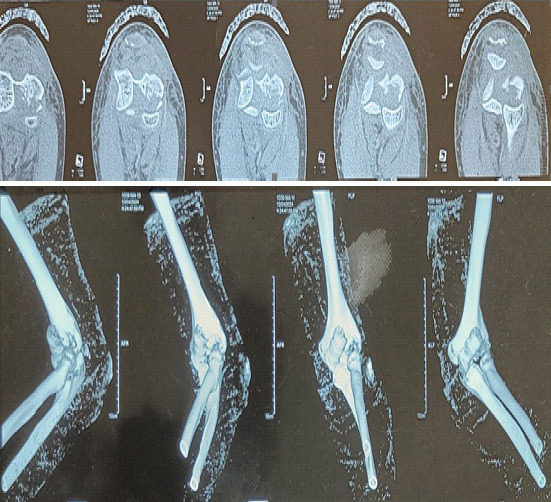

Case report: We present a distinctive case in which an entire capitellum and trochlea were fractured as a single unit in the coronal plane (mimicking McKee type 4 capitellum fractures), along with a DTTA injury in a female patient in her late 40s. This injury was treated using open reduction and internal fixation with cannulated cancellous screws, along with the repair of the DTTA injury.